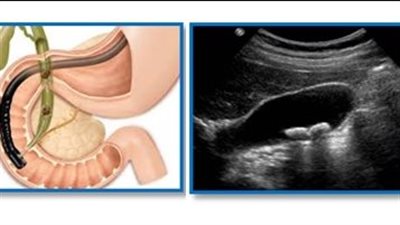

ما فحوصات تشخيص التهاب المرارة؟.. ستة انواع

تفتيت حصوات المرارة بالموجات فوق الصوتية.. كيف يتم؟

تفتيت حصوات المرارة بالمنظار.. متى يتخذ الطبيب القرار؟